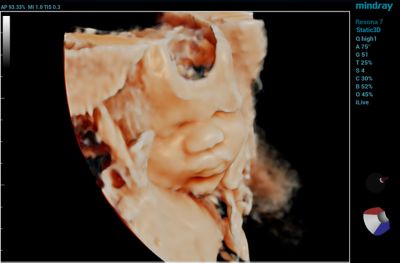

1. High-Resolution Images

Image quality and image-enhancing feature sets are typically top of mind when looking for a new ultrasound machine. The quality of the image directly impacts patient care, so it is important that you select a system that provides the quality you need to arrive at the appropriate diagnoses.

When evaluating a machine, pay careful attention to image resolution. For instance, ensure the machine offers excellent contrast resolution — its ability to distinguish between tissues with different levels of brightness. A high-quality ultrasound machine will show the subtle differences between tissues to enable a precise diagnosis.

Also, consider software features that enhance image clarity and reduce unwanted artifacts — images that don't represent real anatomical structures. This includes image processing algorithms like speckle reduction and spatial compounding, which reduce noise and improve image quality.

• 3D/4D imaging